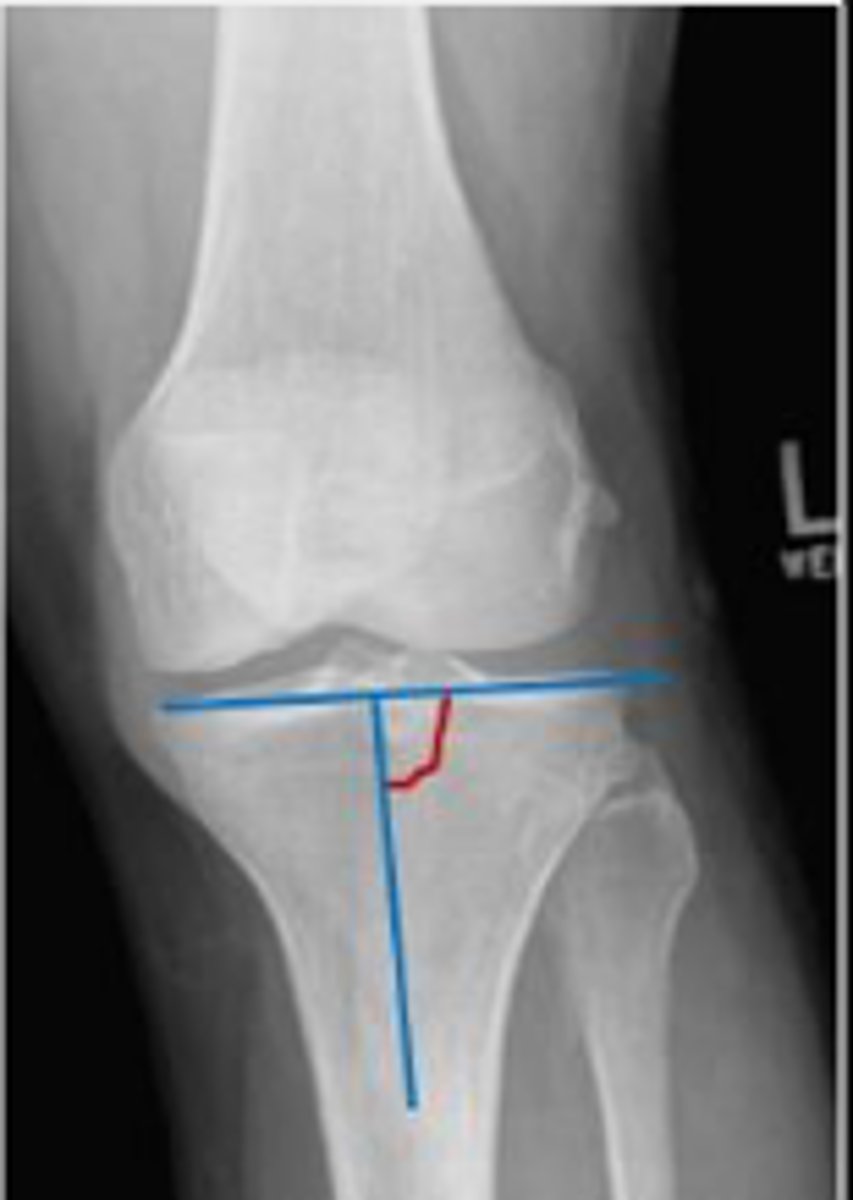

Tibial angle of the left knee

What is the name of the assessment?

Yes

Is this assessment within normal limits?